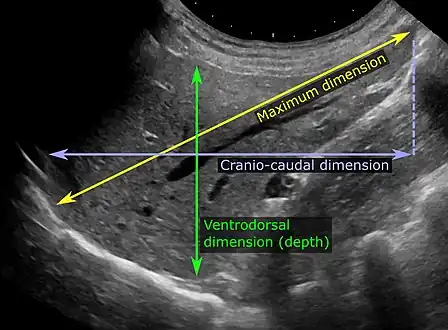

Abdominal ultrasonography of the liver, as a sagittal plane through the midclavicular line, with some standard measurements.[2] -

On abdominal ultrasonography, the liver can be measured by the maximum dimension on a sagittal plane view through the midclavicular line, which is normally up to 18 cm in adults.[2] It is also possible to measure the cranio-caudal dimension, which is normally up to 15 cm in adults.[2] This can be measured together with the ventro-dorsal dimension (or depth), which is normally up to 13 cm.[2] Also, the caudate lobe is enlarged in many diseases. In the axial plane, the caudate lobe should normally have a cross-section of less than 0.55 of the rest of the liver.[2]

Other ultrasound studies have suggested hepatomegaly as being defined as a longitudinal axis > 15.5 cm at the hepatic midline, or > 16.0 cm at the midclavicular line.[16][17]